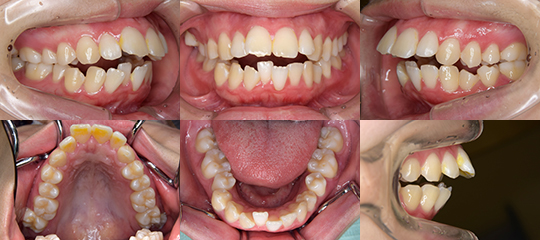

上下顎叢生を伴う上下顎前突(抜歯治療)

⇒治療経過も含む詳細な説明はこちらから

叢生の改善のためではなく、口もと(上下口唇)を引っ込める

(後退させる)ことを目的として上下顎の左右の第一小臼歯を

抜歯した症例です

初診時

上下顎前突 治療前

以下にも上下顎前突の症例の初診時の口腔内写真を示しています。

詳しい治療経過をご覧になられる場合は画像をクリックして下さい。